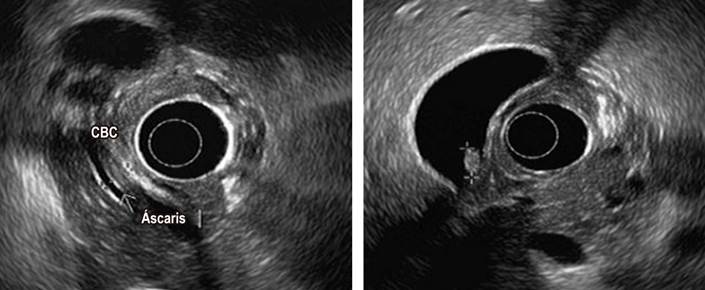

Como estudio complementario, se realizó una ecografía abdominal, en la cual se evidenció la presencia de pólipo vesicular y barro biliar, sin alteraciones a nivel de la vía biliar. Debido al riesgo intermedio de coledocolitiasis, por el aumento de las bilirrubinas totales, la alteración del perfil hepático, la clínica de pancreatitis biliar (Tabla 1) y mayor sensibilidad para microlitiasis, se practicó una ultrasonografía endoscópica que reportó colelitiasis asociada a imagen y fue compatible con AL a nivel de la luz del colédoco, con estructura alargada tubular hiperecogénica, que no daba sombra acústica, e imagen en doble riel (Figura 2). Se indicó un manejo con albendazol (400 mg vía oral, cada 24 h por 3 días) y se efectuó una CPRE, sumada a una papilotomía y a la extracción de áscaris a nivel de la vía biliar, sin complicaciones posoperatorias (Figura 3).